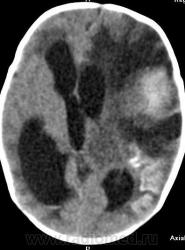

Я думаю, это больше похоже на кровоизлияние - неоднородная структура с гиперденсным компонентом. Плюс ко всему - клиника, судя по всему, с острым началом. Опухоли быстро не растут.

Смущает то, что кровоизлияние как бы в капсуле. А что с извилинами? Пропитывание кровью?

Паразитарная киста - это эхинококк? Образование имеет плотность свежей крови, так что кровоизлияние не вызывает сомнений. Но вот возможно кровоизлияние в опухоль или в результате какой-либо сосудистой патологии, например, ангиоматоза Штурге-Вебера. Насчет течения родов попробую уточнить.

Светлые участки 70 ед Н - плотности крови.

А ведь кровоизлияние есть субарохноидально.

Денди Уокер? Не думаю, хотя надо посмотреть аксиалы ниже уровня намёта. А пока явно вижу признаки Sturge-Weber syndrome - encephalotrigeminal angiomatosis синдром со всеми вытекающими.